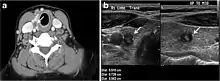

Fig. 4. A 45-year-old male patient presented with anterior mediastinal metastatic PTC lesions and occult primary on imaging. Histopathology examination of the resected thyroid gland revealed micro-foci of PTC; the largest, in the isthmus, measured 4 mm. a transverse greyscale ultrasound of the thyroid demonstrates homogeneous gland with normal echogenicity and size. No focal lesion or micro-calcifications. b Non-enhanced CT scan obtained as part of PET/CT examination shows a heterogeneous, large, relatively dense anterior mediastinal mass (white arrow) with peripheral calcification (arrowheads). Thyroid gland has normal CT appearance with no abnormal FDG uptake (not shown).[1]

Fig. 7. A 51-year-old female patient post total thyroidectomy for PTC with elevated thyroglobulin measurement. an Axial non-enhanced CT scan of the neck at the level of the thyroid bed demonstrates a well-defined, rounded, homogenously dense soft tissue situated between the trachea and left internal jugular vein (white arrow). b Transverse ultrasound image of the neck demonstrates a well-defined, homogeneous, hypoechoic soft tissue nodule measuring 6 mm (white arrow) with no detected micro-calcifications. Biopsy showed a predominantly residual normal thyroid tissue with micro-foci of PTC.[1]